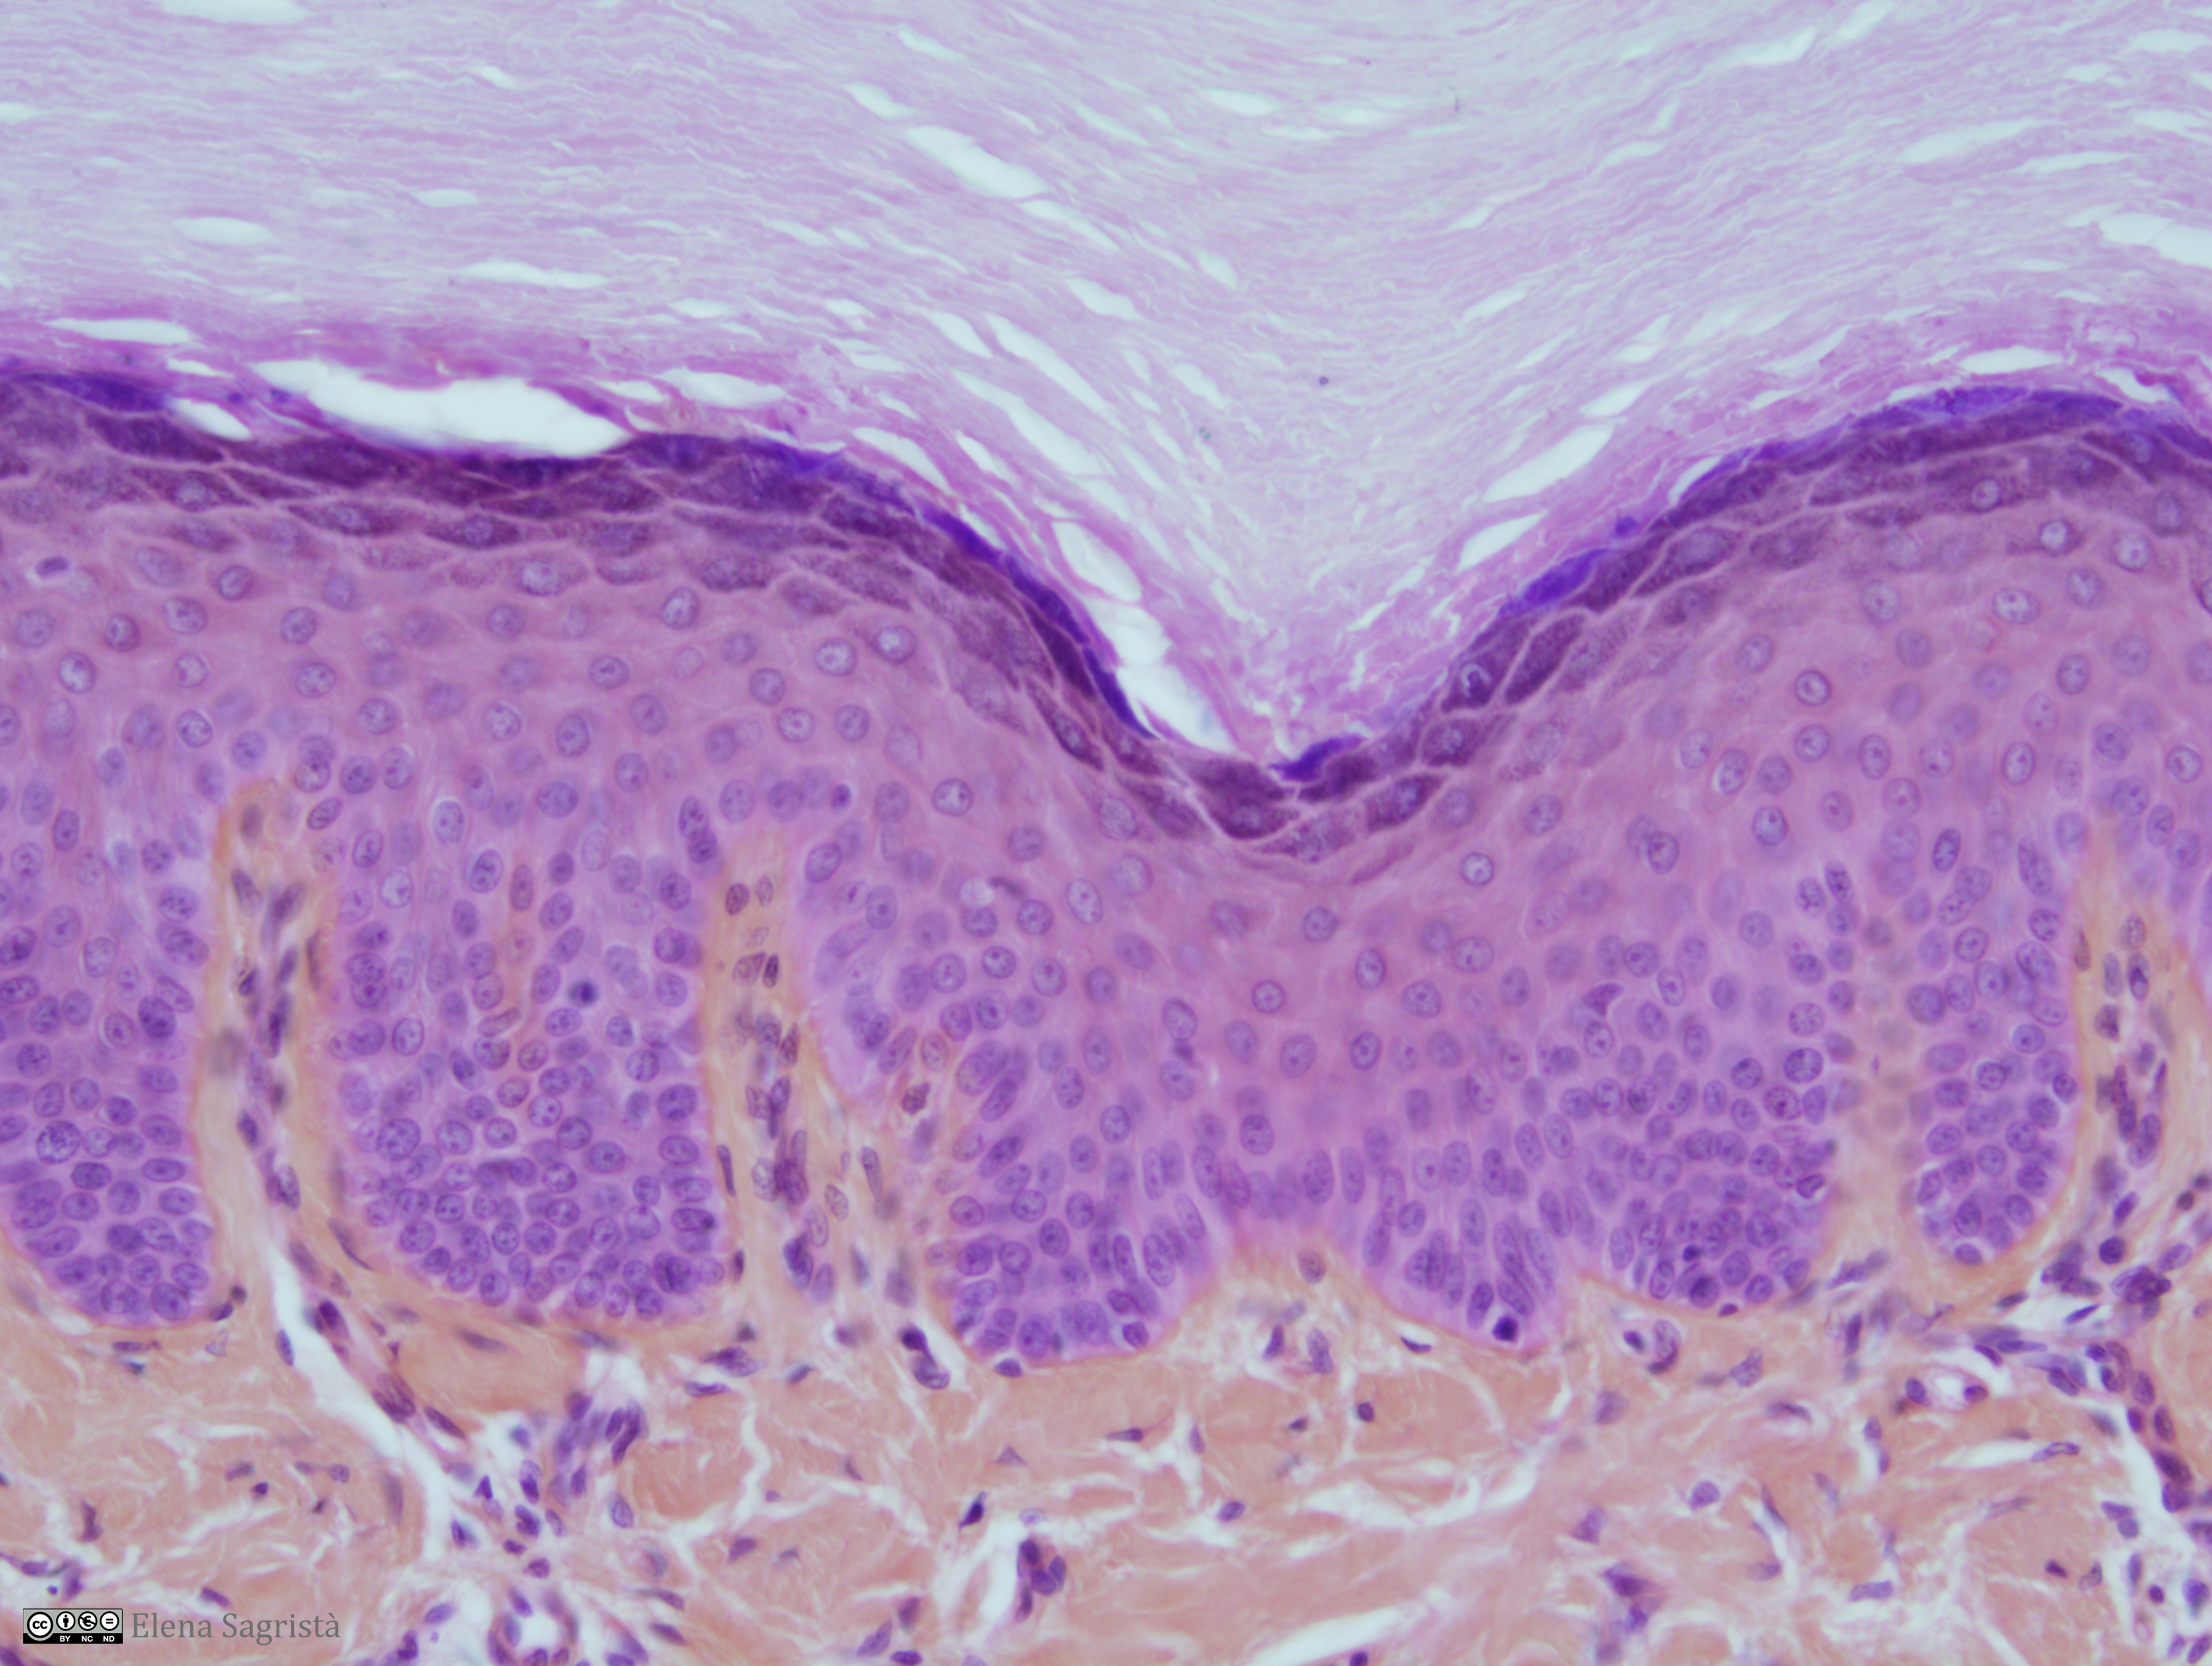

Histologia imatges: 01 Teixit epitelial

Imatges de preparacions histològiques de teixit epitelial. Microscopia òptica.